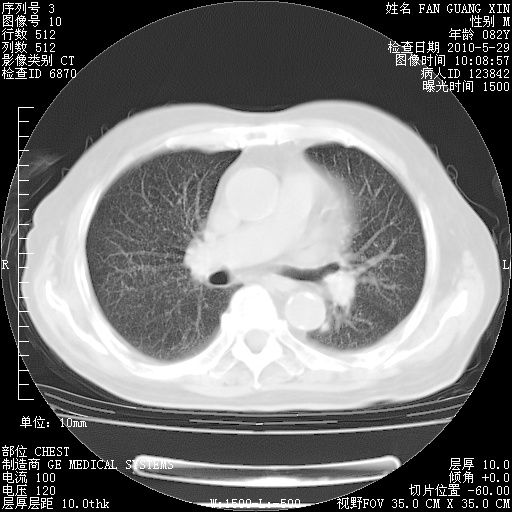

再治疗10天后的肺部CT 纵膈窗